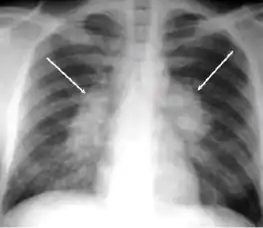

5. Hilar or mediastinal lymphadenopathy (bihilar lymphadenopathy) - Enlargement of lymph nodes in one or both hila or within the mediastinum, with or without associated atelectasis or consolidation.

-

Chest x-ray showing bilateral hilar adenopathy of primary pulmonary TB